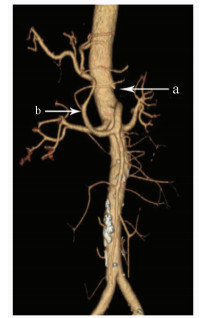

Hepatic Artery; Mesenteric Artery, Superior; Pancreatic Neoplasms

Allamyradov Aly, Yan DU, Tongtai LIU, Xiaodong WANG, Kai YAO

2021, 37(1): 163-164. DOI: 10.3969/j.issn.1001-5256.2021.01.034

Abstract(854) HTML (272) PDF (2322KB)(44)

Abstract: